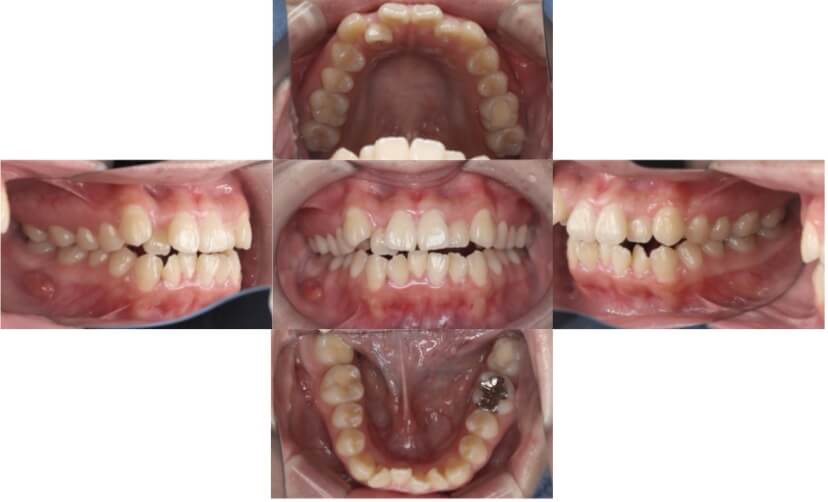

BEFORE

AFTER

上下顎前突、叢生(上下出っ歯、上下の前歯のガタガタ)のケースです。

装置はラビアル(上下表側)で、上下顎の小臼歯を4本抜歯を行っています。抜歯したスペースを使って、上下の前歯の後方移動と叢生(ガタガタ)の改善を行っています。

主訴 前歯のガタガタと口元がでているのが気になる。

年齢・性別 30歳 女性

お住まいの地域 東京都大田区

治療方針 抜歯スペースを利用して上前歯の叢生(ガタガタ)と口元突出の改善

抜歯部位 上下顎左右第一小臼歯

使用装置 ラビアル(上下表側)、顎間ゴム

治療期間 1年11か月

治療回数 13回

リテーナー クリアリテーナー